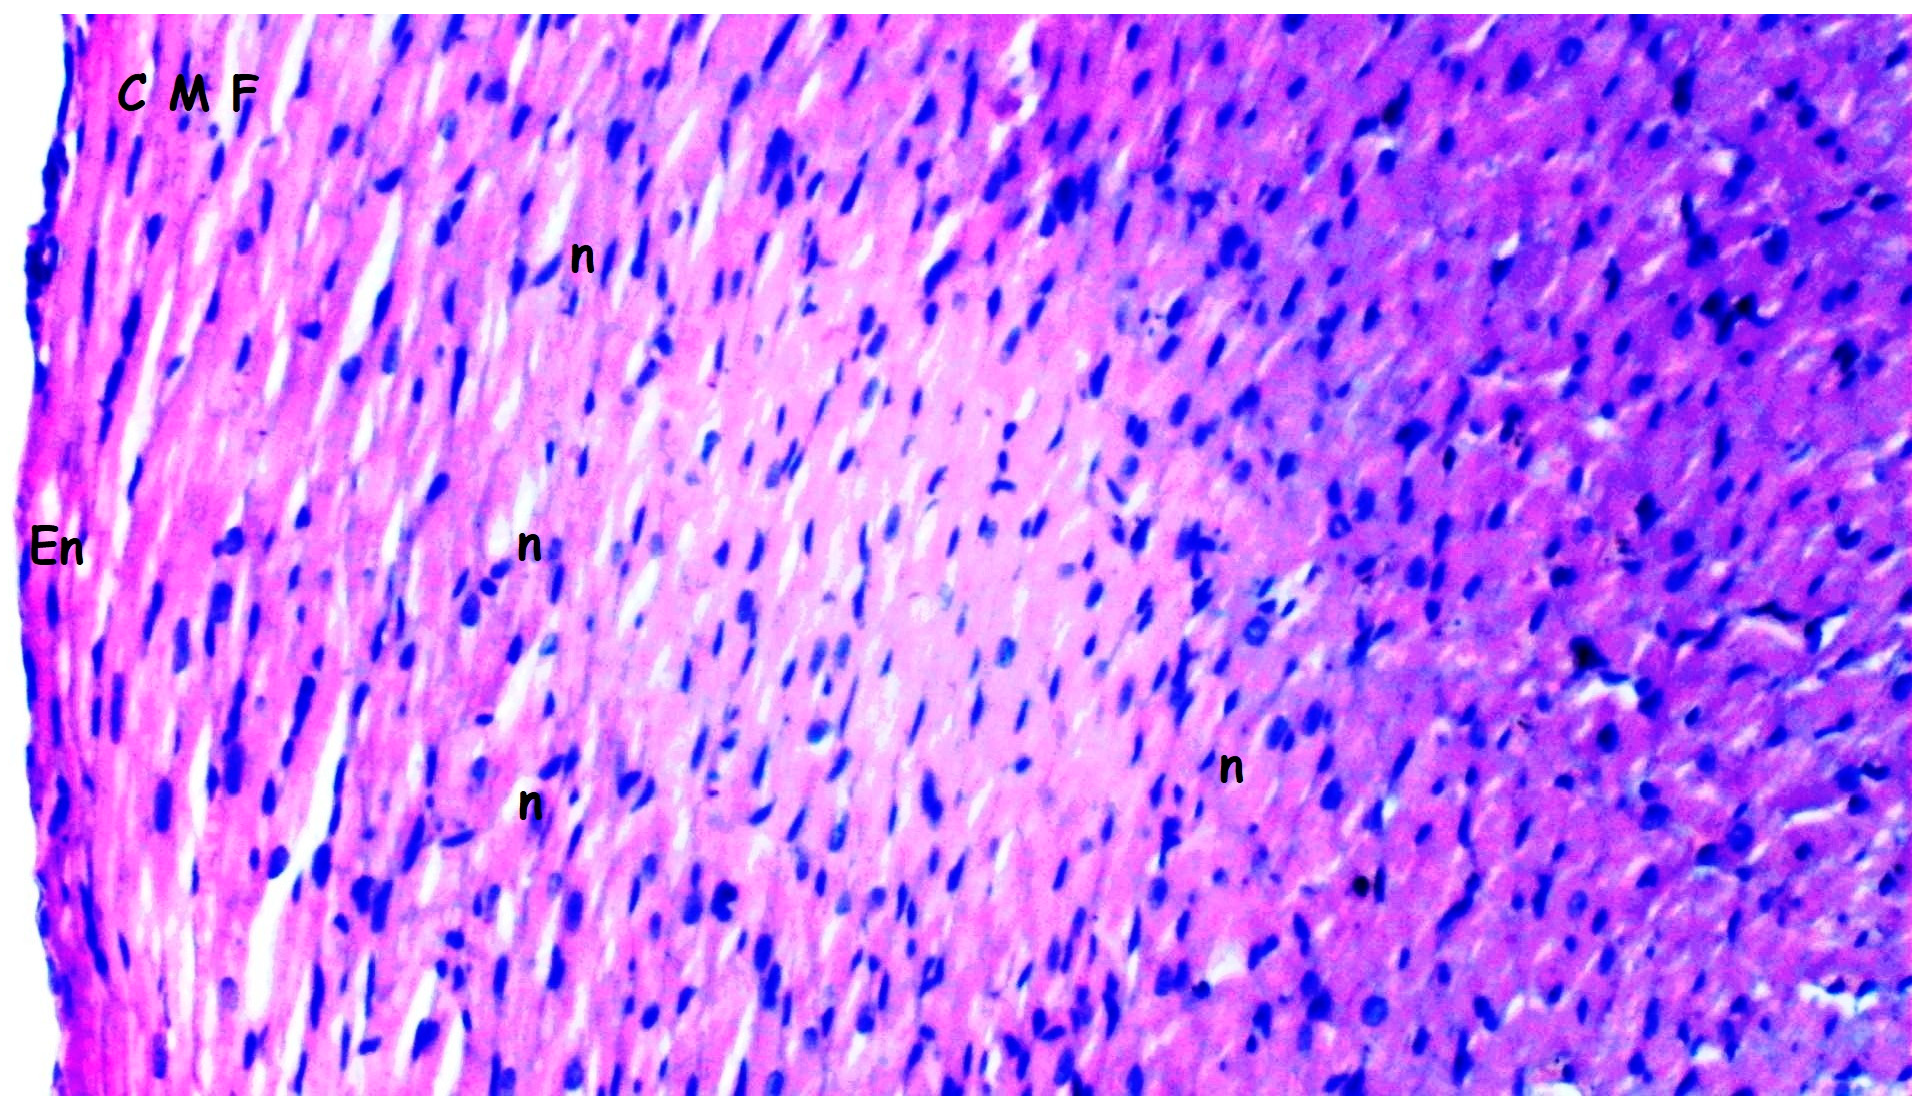

3.1. Histopathologic Findings

| [23,33] Myocardial disorganization | 0.50 ± 0.22 | 0.50 ± 0.22 | 1.25 ± 0.16 *,& | 0.63 ± 0.18+ | 0.028 |

| Inflammation and neutrophil infiltration | 0.33 ± 0.21 | 0.50 ± 0.22 | 1.25 ± 0.16 *,& | 0.63 ± 0.18+ | 0.012 |

| Interstitial fibrosis | 0.33 ± 0.21 | 0.50 ± 0.22 | 1.25 ± 0.16 *,& | 0.75 ± 0.16 | 0.010 |

| Interstitial edema | 0.33 ± 0.21 | 0.50 ± 0.22 | 1.25 ± 0.16 *,& | 0.63 ± 0.18 + | 0.012 |

| Swelling of myocardial cells | 0.33 ± 0.21 | 0.33 ± 0.21 | 1.13 ± 0.13 *,& | 0.63 ± 0.18 + | 0.013 |

| Myocardial necrosis | 0.17 ± 0.17 | 0.33 ± 0.21 | 0.75 ± 0.16 | 0.63 ± 0.18 | 0.126 |